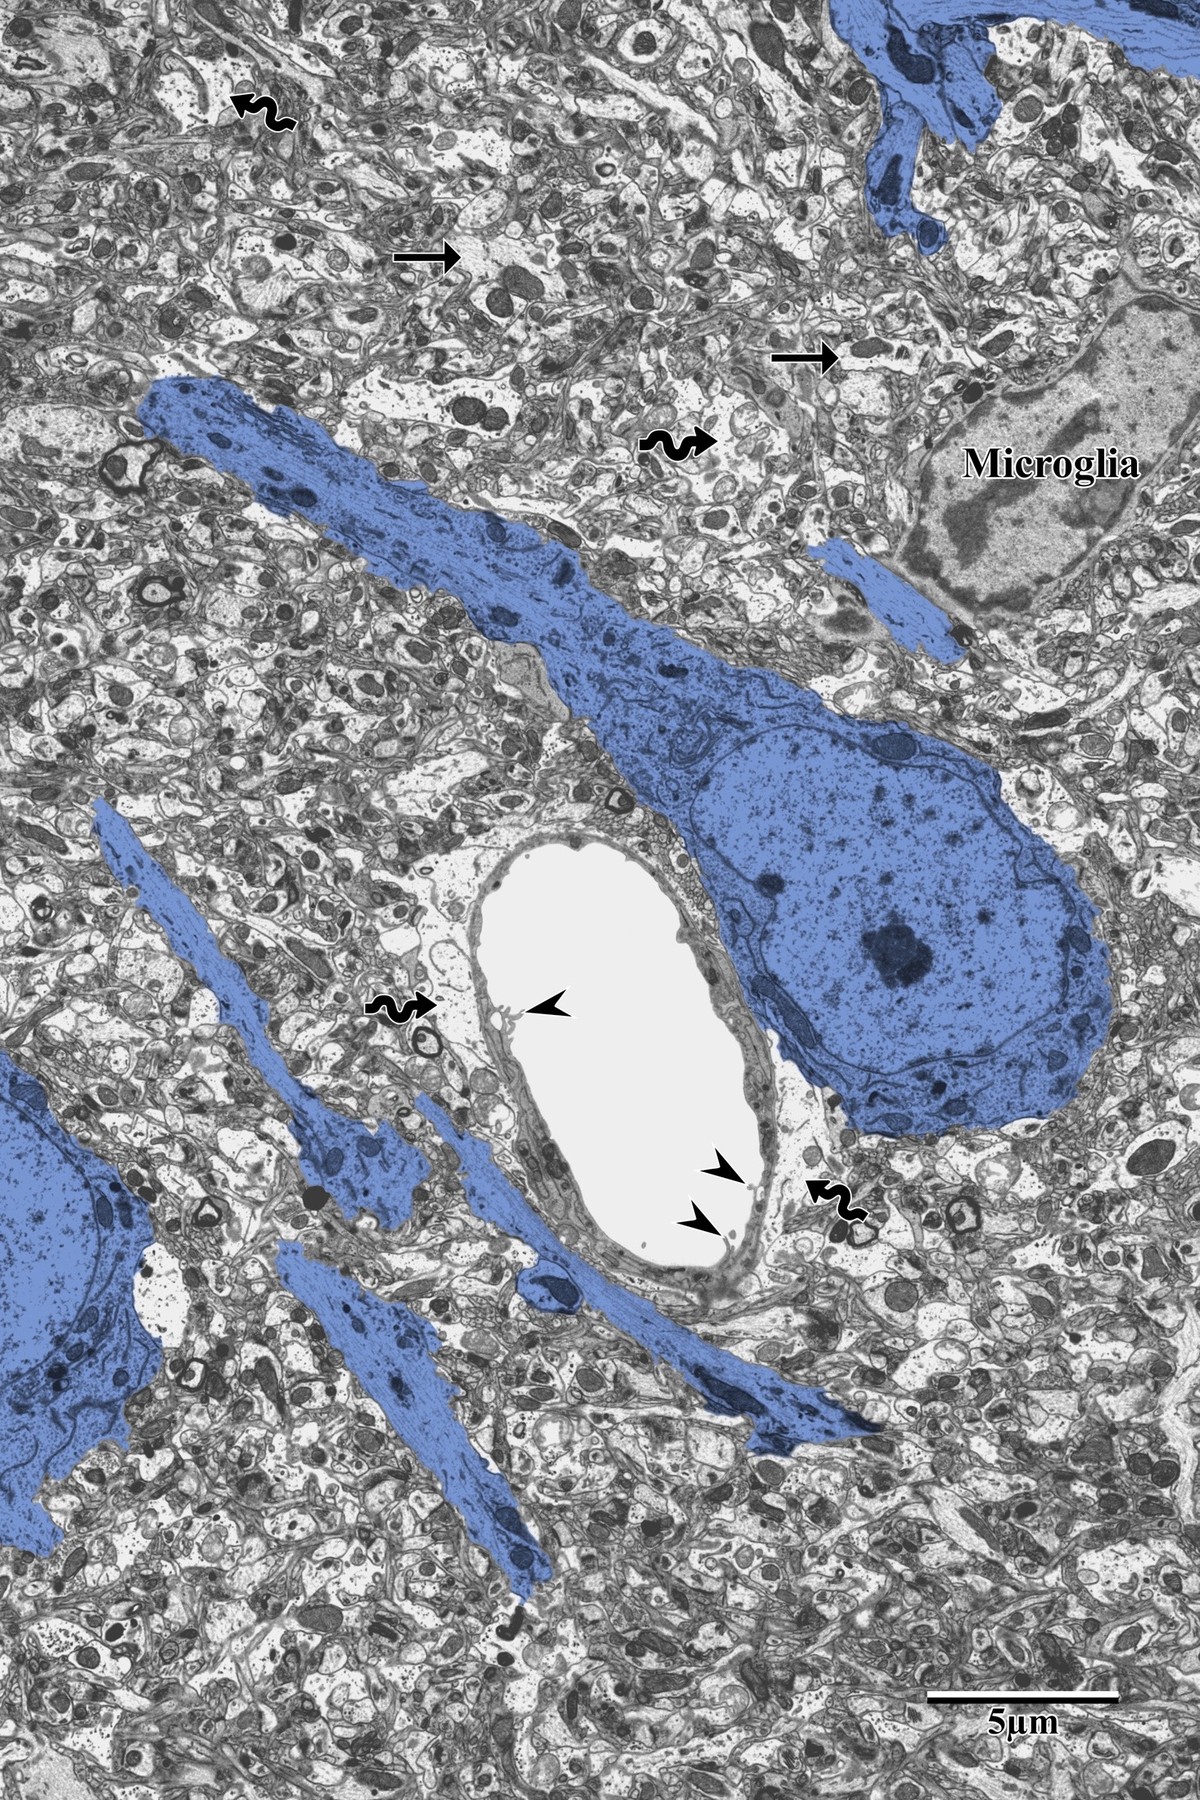

Peri-Infarct Neuronal Degeneration

Progressive neuronal degeneration is observed with increasing proximity to the infarct core. Distal PI neurons show early cytoplasmic darkening with partial organellar preservation and microglia encroachment. Proximal PI neurons display advanced degeneration — swollen mitochondria, disrupted endoplasmic reticulum, and vacuolization of the surrounding neuropil.

Distal peri-infarct neuron showing early ischemic changes with microglia

Distal peri-infarct zone: neurons (blue) showing early ischemic changes with microglia encroachment (labeled). Note the reduced dendritic complexity compared to control tissue. From Bayati, BSc Honours Thesis 2018.